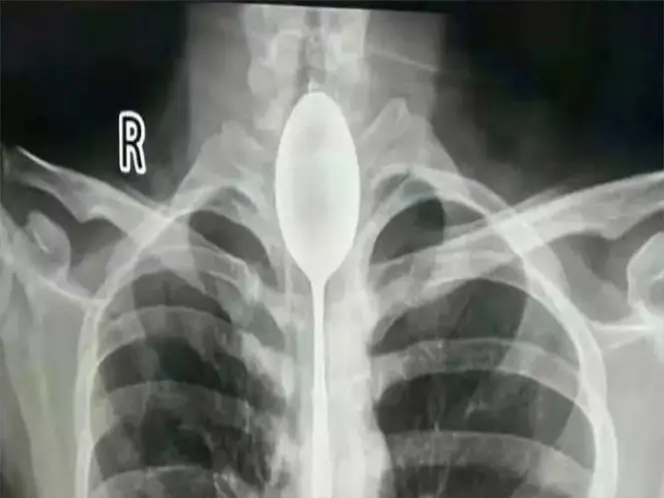

Medios internacionales reportaron el curioso caso de un hombre, que vivió un año entero con una cuchara de 20 centímetros que estuvo atorada en su esófago. Los médicos que le sustrajeron el extraño objeto no salían de su sorpresa.

El insólito caso se registró en la ciudad de Urumchi en la región de Sinkiang cuando el ciudadano de apellido Zhang, acudió de urgencia al hospital debido a fuertes dolores en su pecho y dificultad para respirar.

De acuerdo con el relato del afectado contado en Daily Mail, se tragó la cuchara durante una borrachera cuando apostó con sus amigos. Su objetivo era retirar el cubierto con una cuerda, sin embargo, falló y jamás pudo hacerlo.

Al realizarle una radiografía, los doctores quedaron impactados al ver el cubierto.

Afortunadamente, el objeto pudo ser retirado vía bucal sin necesidad de intervención quirúrgica.